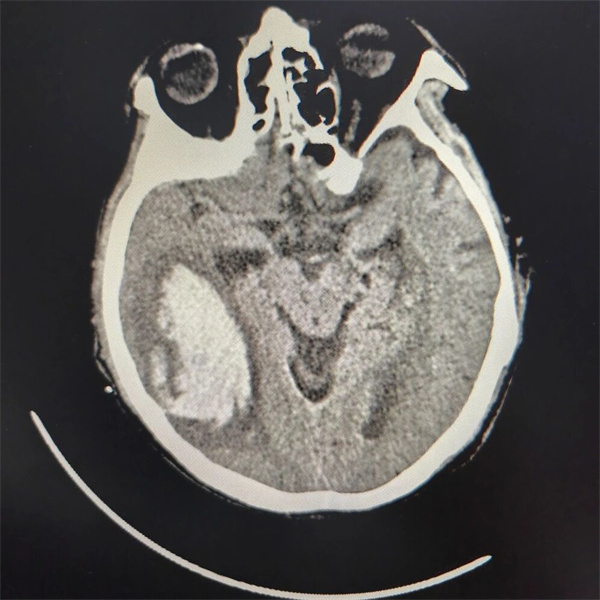

11月1日,吴爷爷因“头晕伴肢体无力6小时”被家属搀扶着走进北京老年医院急诊急救中心,彼时老人已出现意识模糊迹象。头颅CT结果如惊雷般炸响:

▲ 患者头颅CT影像

右侧颞枕叶脑出血,出血量高达75.7ml,中线结构明显移位,脑室被压迫得几近变形。神经外科樊玉良主任火速会诊后,表情格外凝重:“脑出血量超30ml就具备手术指征,75.7ml已是大量出血,加上中线移位,患者随时可能因脑疝引发呼吸心跳骤停。”